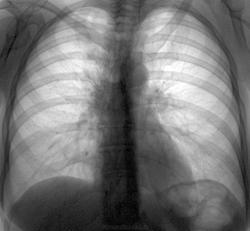

Сегодняшние флюшки. Женщина жалуется на простуду (кашель, субфибрилитет), бронхиты часты, пневмоний никогда не было. Думаю, без онко тут не обойдется, хотя в лоб пока не высказал. Намекал на КТ - нет денег. Сошлись на пневмонии с дальнейшим контролем. Какие будут мнения?

Увеличение лимфоузлов средостения, слева тоже непорядок.

Поставим пока точку в этом случае. Женщина сделала флюороконтроль только прямо (хоть я ей раньше говорил, что-бы делала контроль прямо и правым боком), мой компаньон поставил N с положительной динамикой. Не буду рыть...

Ура, вылечилась

Лимфоаденопатия при ОРВИ.

Всё хорошо,что хорошо кончается.